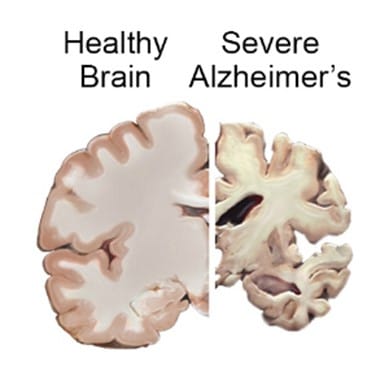

Patients in this stage have severe memory and language impairment, such as anomia, paraphrasing errors, a decline in spontaneous verbal output, and a propensity for circumlocution to avoid forgotten words. Wandering in familiar settings and constructional apraxia result from impaired visuospatial ability.

Delusions occur in 20–40% of patients. Although patients also have olfactory and auditory hallucinations, visual hallucinations are more frequent. Nearly 50% of patients engage in disruptive behaviors. Patients also experience interrupted sleep and lose their regular circadian sleep-wake pattern.

Alzheimer disease is initially associated with decreased memory; nevertheless, the individual may acquire significant cognitive and behavioral symptoms such as depression, rage, anxiety, irritability, sleeplessness, and paranoia with time.

Most individuals will require assistance with daily living activities as the disease advances. Even walking becomes difficult at some point, and many patients cannot eat or suffer from swallowing issues, leading to aspiration pneumonia.